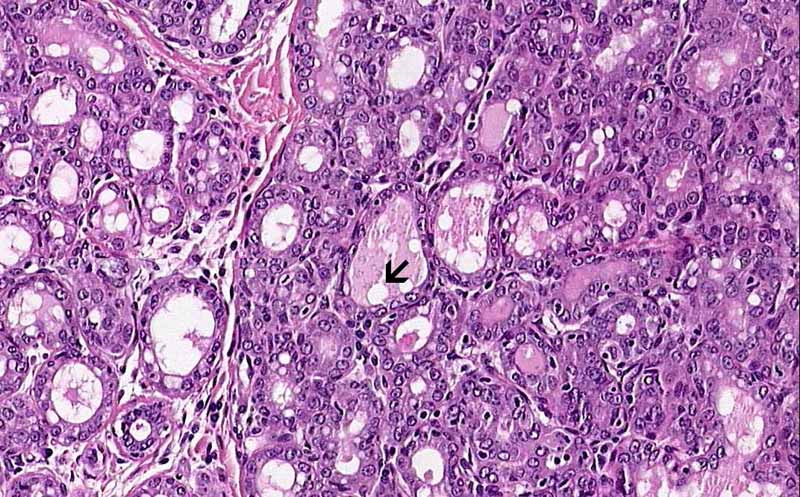

• On higher magnification, the glands have a moderate variation in size and some of them are distended. Vacuoles are seen in the content as well as in the cytoplasm of the cells. These vacuoles represent fat of the milk (Area 1 and 2).

Area 2: The changes are similar in different areas. Note the bubbly content of the glands with vaculoles representing lipid droplets.